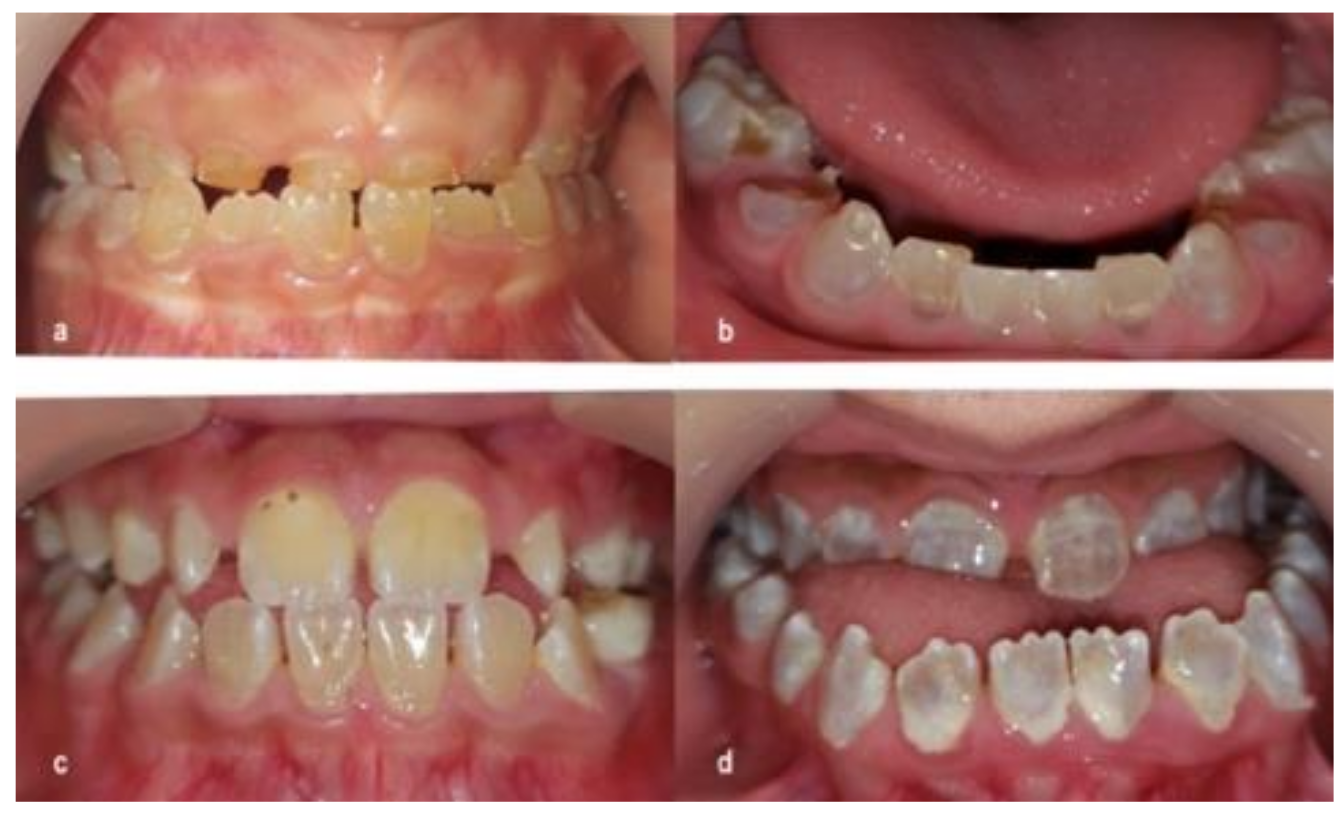

3.1. Dentinogenesis Imperfecta

4.1. Dentinogenesis Imperfecta